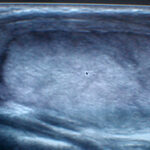

Ultrasound of the thyroid and neck with color Doppler

Ultrasound-guided thyroid puncture with cytological analysis of samples